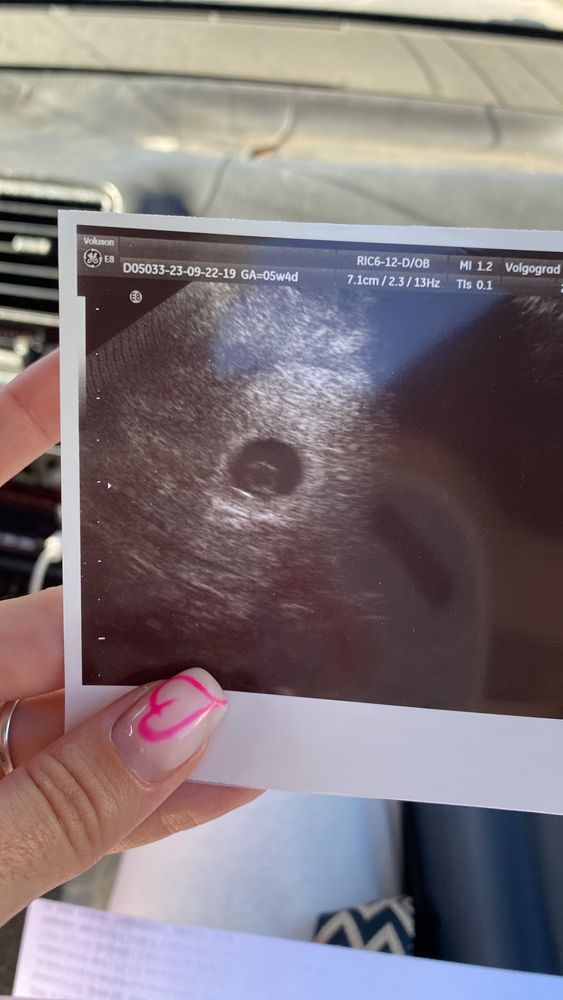

Наше первое узи🥰

У вас пя маленькое для 6 недель и для такого эмбриона

Ирина ツ, а я поняла что узи было на сроке 5,4. А сейчас уже 6,3

Виктория, а да,не заметила,22.08 написано дата исследования,тогда нормально,я просто подумала что в 6,3 такое пя 9 мм,это мало,а для 5 недель норм

Ирина ツ, думаю нет, узи было в 5недель и 4дня в норме 7-8мм, у меня 9мм😊

Мы узисты называем эту картинку кольцо с бриллиантом 💍 очень красиво